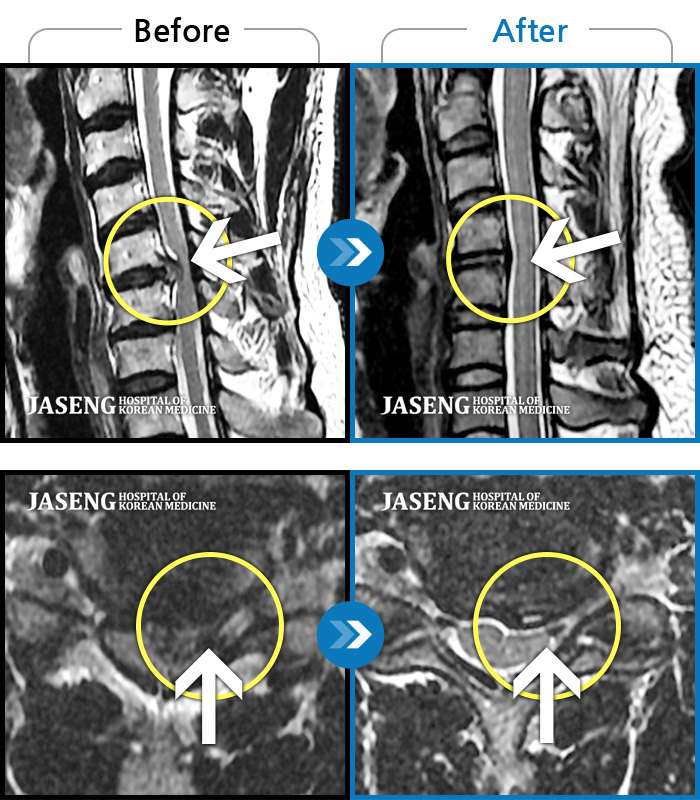

허리디스크

부천 · 최요섭 원장

양측 허리와 골반 통증, 양측 다리 저림

촬영시기

2018.05.17 ~ 2019.10.17

2019.12.13

조회수 6,156